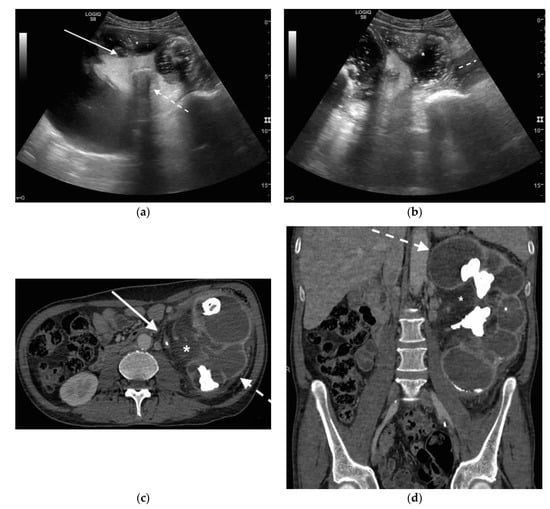

3. Ultrasound

4. CT